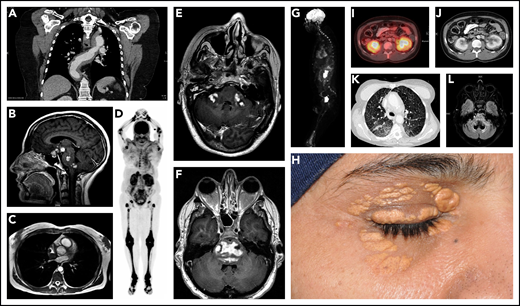

ECD has diverse organ system manifestations, with varying frequencies based on different institutional case series (Figures 2-4; Table 2).30-43 It is crucial for clinicians to be familiar with the manifestations due to their implications in diagnosis and prognostic staging of the disease. It is important to rule out concomitant myeloid neoplasms among ECD patients due to their high rates of co-occurrence.21,44

Diverse manifestations of ECD. (A) Coronal postcontrast chest computed tomography (CT) demonstrates extensive soft tissue sheathing of the thoracic aorta. (B) Enhancing lesions in the hypothalamic pituitary axis (HPA), brainstem, and cerebellar peduncle is shown in sagittal gadolinium enhanced T1 magnetic resonance imaging (MRI). (C) Three-dimensional fast imaging using steady-state acquisition (3D-FIESTA) MRI of the heart showing right atrial mass from ECD. (D) Maximal intensity projection (MIP) of 18F-fluoro-deoxyglucose (FDG)–positron emission tomography (PET) demonstrates typical hypermetabolic ECD lesions throughout the appendicular skeleton with greatest activity of the disease in the legs. (E) Irregular bilateral enhancing of ECD lesions in the middle cerebellar peduncles are demonstrated by postgadolinium axial T1 MRI. (F) Expansile irregularly enhancing ECD lesions in the pons seen on postgadolinium axial T1 MRI. (G) MIP of FDG-PET demonstrating ECD lesions with increased uptake in distal femur, orbit, multilevel thoracolumbar spine roots, and right atrium. (H) Periorbital xanthelasmas from ECD. (I-J) “Hairy kidney” hypermetabolic and contrast-enhancing perinephric infiltrates are shown on axial-fused FDG PET-CT and contrast-enhanced axial CT scan. (K) High-resolution axial CT scan image of the chest demonstrating reticulonodular opacities from ECD. (L) Atrophic or neurodegenerative changes in the brainstem and cerebellum are shown by axial T2-FLAIR MRI.